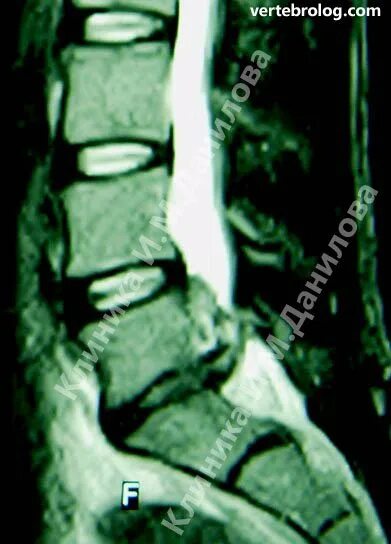

Операция удаление грыжи l5 s1